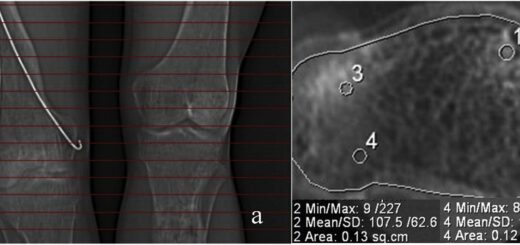

When the soft tissue procedure was accomplished, two opposing Kirschner wires with stoppers were placed in metatarsals bones in the horizontal plane. The wires were fixed to two frames on the plantar aspect of the foot and the frames connected with rods. Then, four distraction rods with hinges were attached to the distal support. After that, new 1 mm wires were inserted into the medial phalanx of the 2nd, 3d, 4th, and fifth toes, U-shaped and fixed to the rod connected with the frames. Finally, acute distraction was performed using the rods to maintain normal toes position. overall operating time was 90 minutes.